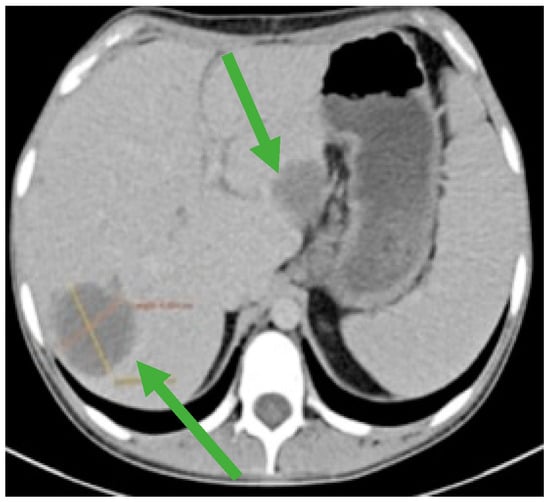

Figure 4.

CT scan showing liver metastases in numerical and dimensional progression (green arrows).

During the maintenance therapy with oral etoposide, the plasma beta HCG was highly increased (6228 mIU/mL), so we decided to start third line chemotherapy with GOP (gemcitabine 800 mg/sqm day 1 and 8, paclitaxel 80 mg/sqm day 1 and 8, oxaliplatin 130 mg day 1, q3w). After five cycles, we observed a new biological and imagistic progression (Figure 3 and Figure 4) in the size and number of the liver and lung metastases that appeared.